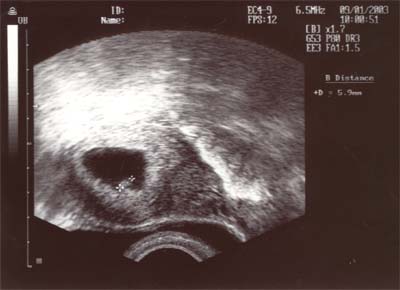

Heute ist der Termin bei der Frauenärztin. Mama ist sowas von aufgeregt...Und dann, beim Ultraschall - oh, was ist das - hallo Mama - hier bin ich - du siehst mein kleines Herzchen schlagen - DU BIST SCHWANGER - nee,nee - Doch ehrlich - Wir sind in der 6. Woche schwanger, lt. US . Mama hatte voll die Tränen in den Augen, als Sie mich sieht - Freudentränen.

Das erste Ultraschallbild von mir.

Da bin ich 5,9mm gross - ein Pünktchen halt -

Für Mama und Papa bin ich jetzt immer Pünktchen.

Dieses Bild ist sechs Tage später gemacht worden.

In dieser Zeit bin ich 0,9mm gewachsen - schon ein etwas grösseres Pünktchen...